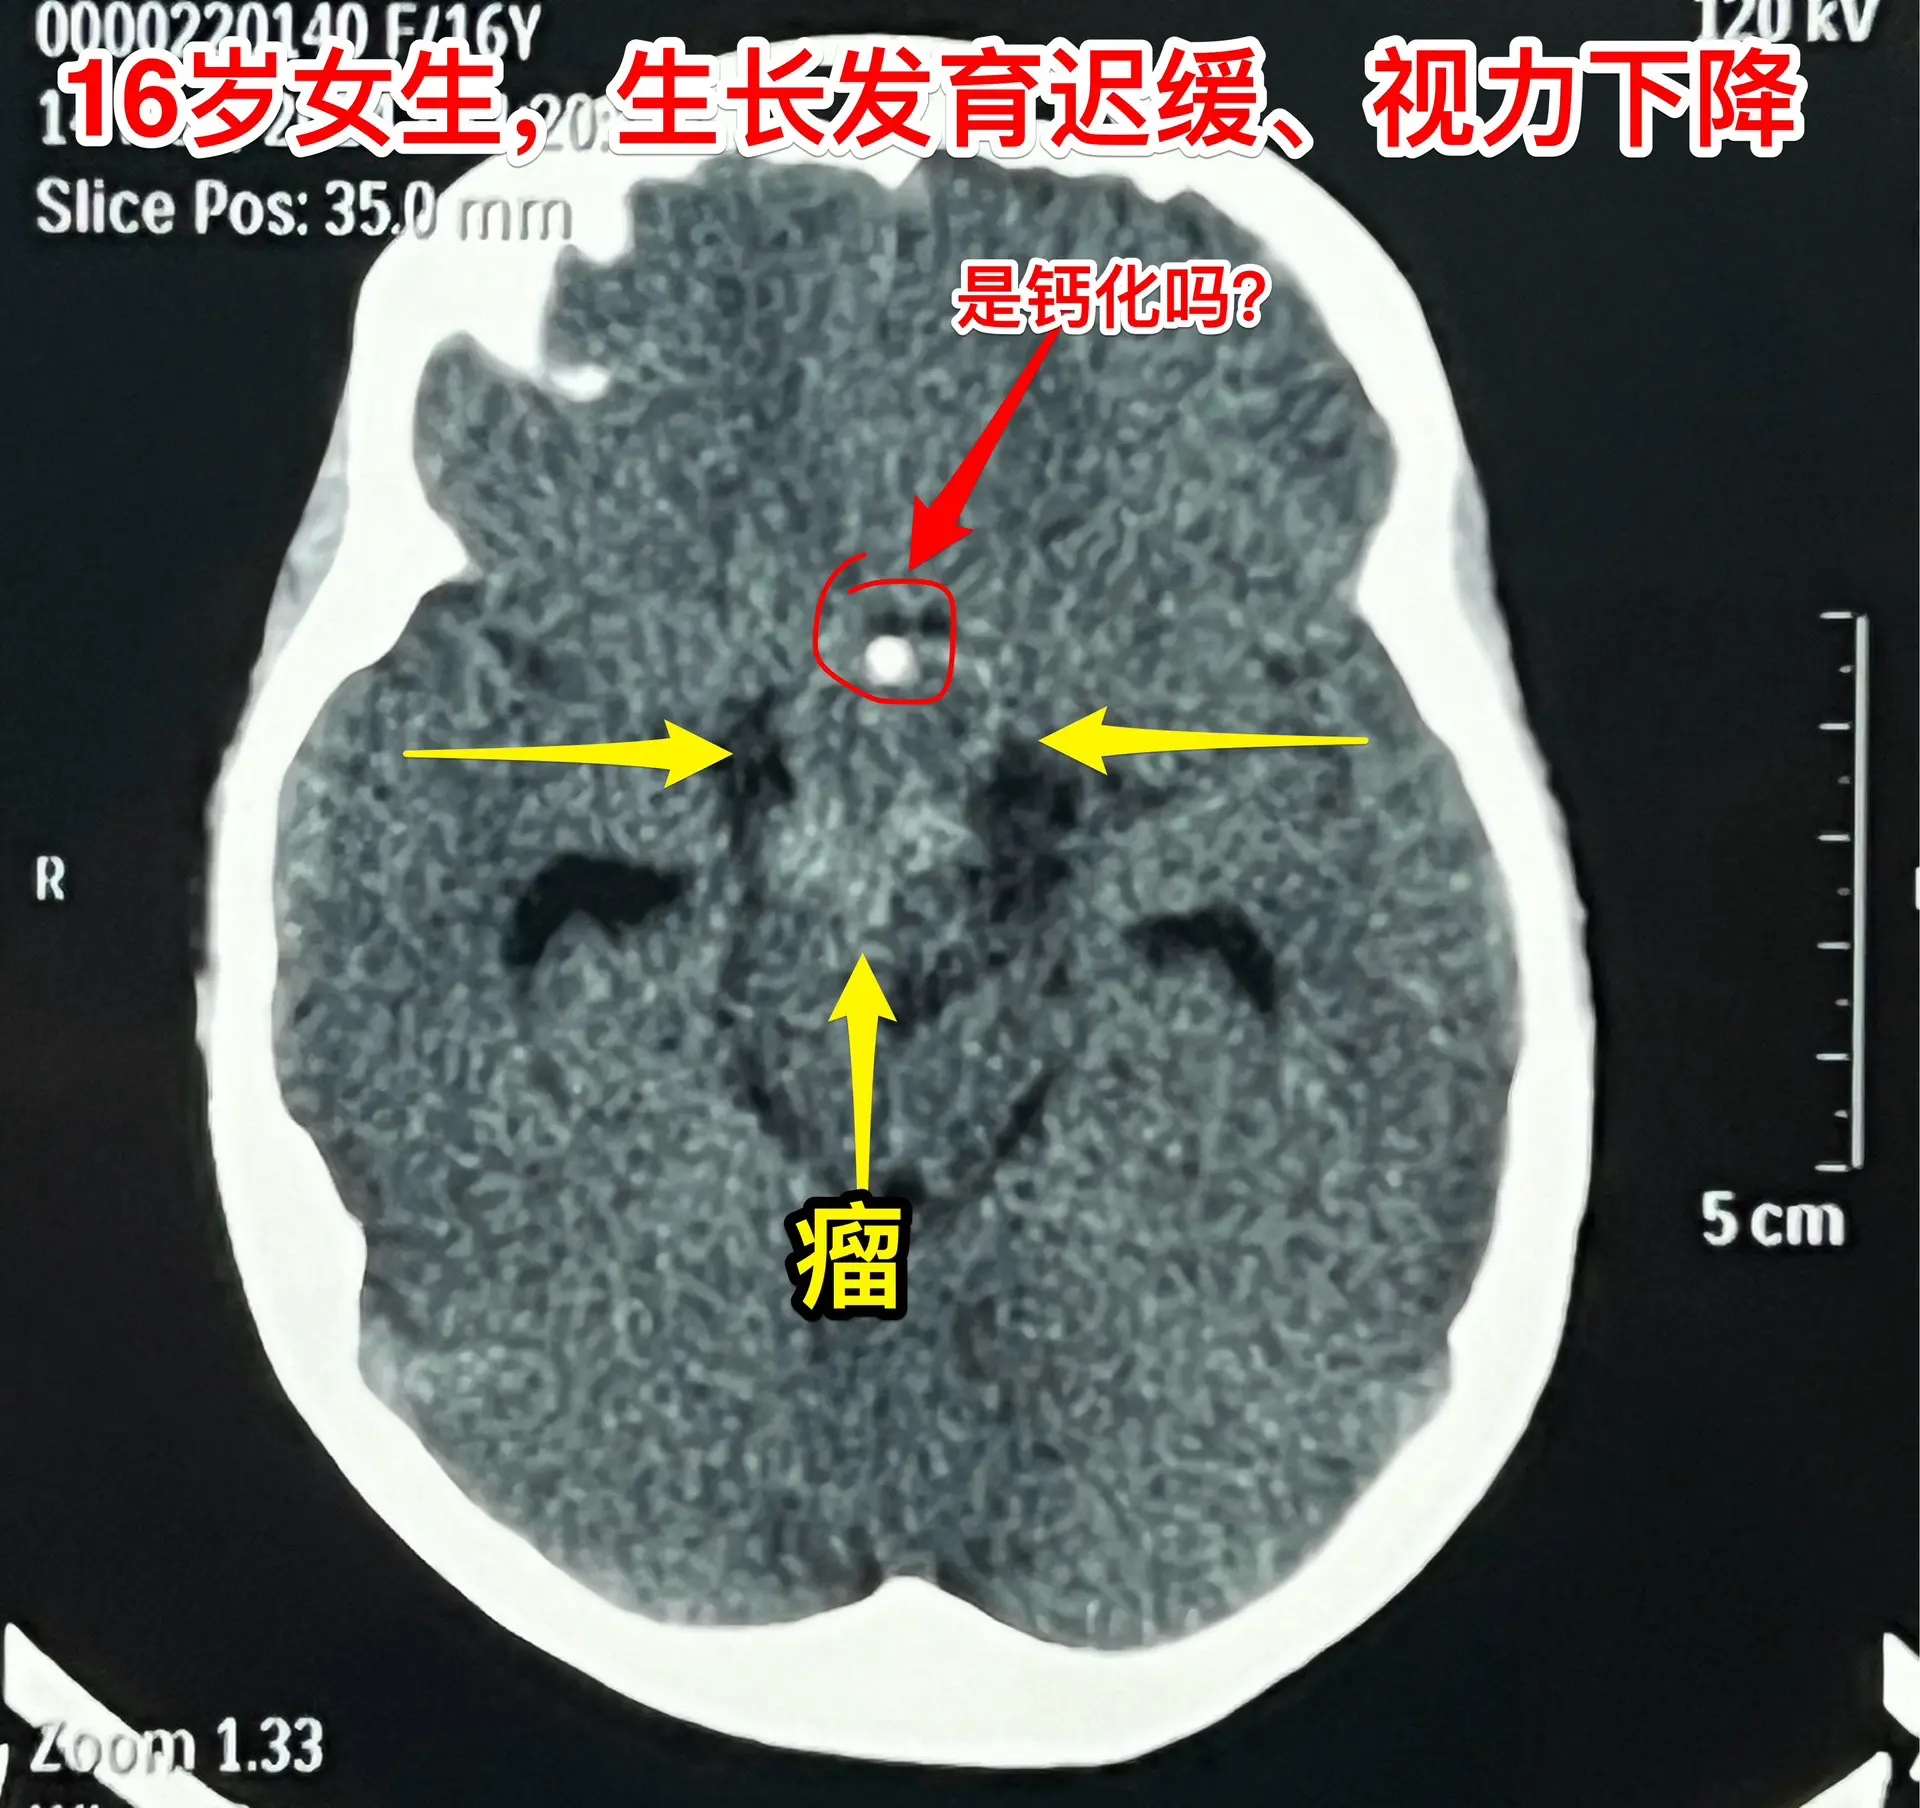

16岁女生在10岁时就有生长发育迟缓症状。16岁衡阳市女生,现在身高才120厘米,体重才21公斤。初中毕业后就辍学了! 她在10岁时就有生长发育迟缓症状,到医院去检查发现生长激素分泌不足。没有找出具体原因,也没有注射生长激素治疗。 近一年有头痛症状,视力也下降了。作磁共振发现长了脑部肿瘤,才到北京来找我作手术。肿瘤体积大,没有钙化,是颅咽管瘤吗? 昨天在手术过程中,取出病变标本作快速冰冻病理检查,报告为乳头型颅咽管瘤。这种类型的颅咽管瘤在小孩子中十分罕见。 我多次提醒家长,如果发现小孩子的生长发育有异常,要尽早到医院去检查,找出原因,尤其是针对脑部要作磁共振检查,排除脑部肿瘤。对于生长激素缺乏者,不能不管原因,轻易注射生长激素治疗。